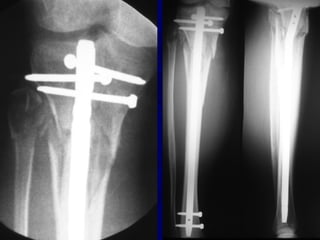

Expanded Indications • Proximal1/3 • Distal 1/3 • Increased Problems

• 53.

• Proximal Fractruesare technically more challenging • Prone to Valgus & • Pro-curvatum deformities

Technique • Screws placedon concave side of deformity.

• 56.

Blocking (Poller) Screws •Functionally narrow im canal • Increase strength and rigidity of fixation

The Use ofPoller Screws as Blocking Screws in Stabilising Tibial Fractures Treated with Small Diameter Nails • 21 patients • All healed within 3-12 months • Mean alignment 1 degree valgus, antecurvatum 2 degrees. Krettek C, et al. JBJS 81B: 963, 1999

• 58.

• Entry Sitefor Proximal fractures Critical • Reference is Lateral Tibial Spine

• 63.

Reduction of DistalTibial Fractures • Distractor • Joy Stick • Fibular Plating • Calcaneal Traction

Proximal and DistalCases Courtesy of R. Winquist M.D. Seattle, Wa.